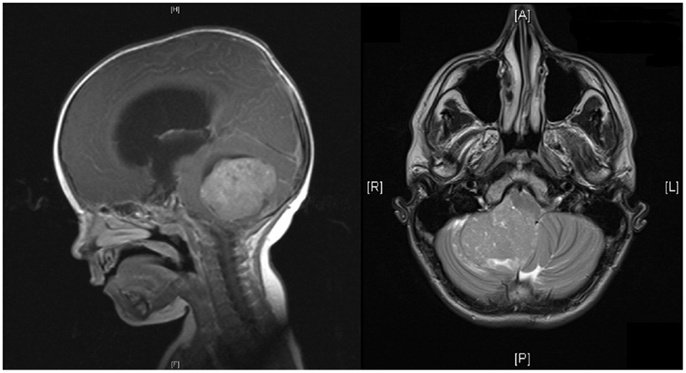

髓母细胞瘤,这种起源与胚胎残余细胞的肿瘤可发生在脑组织的任何部位,但多数生长在四脑室顶之上的小脑蚓部,是中枢神经系统恶性程度较高的肿瘤之一。虽然每10万人中发病才不到1个人,但具有预后差、生长快、易转移的特点。即使手术切除掉肿瘤,3-6个月肿瘤就可能复发,长到原来大小。髓母细胞瘤喜欢“光顾”10岁以下的儿童,且男孩发病率多是女孩的2倍多。